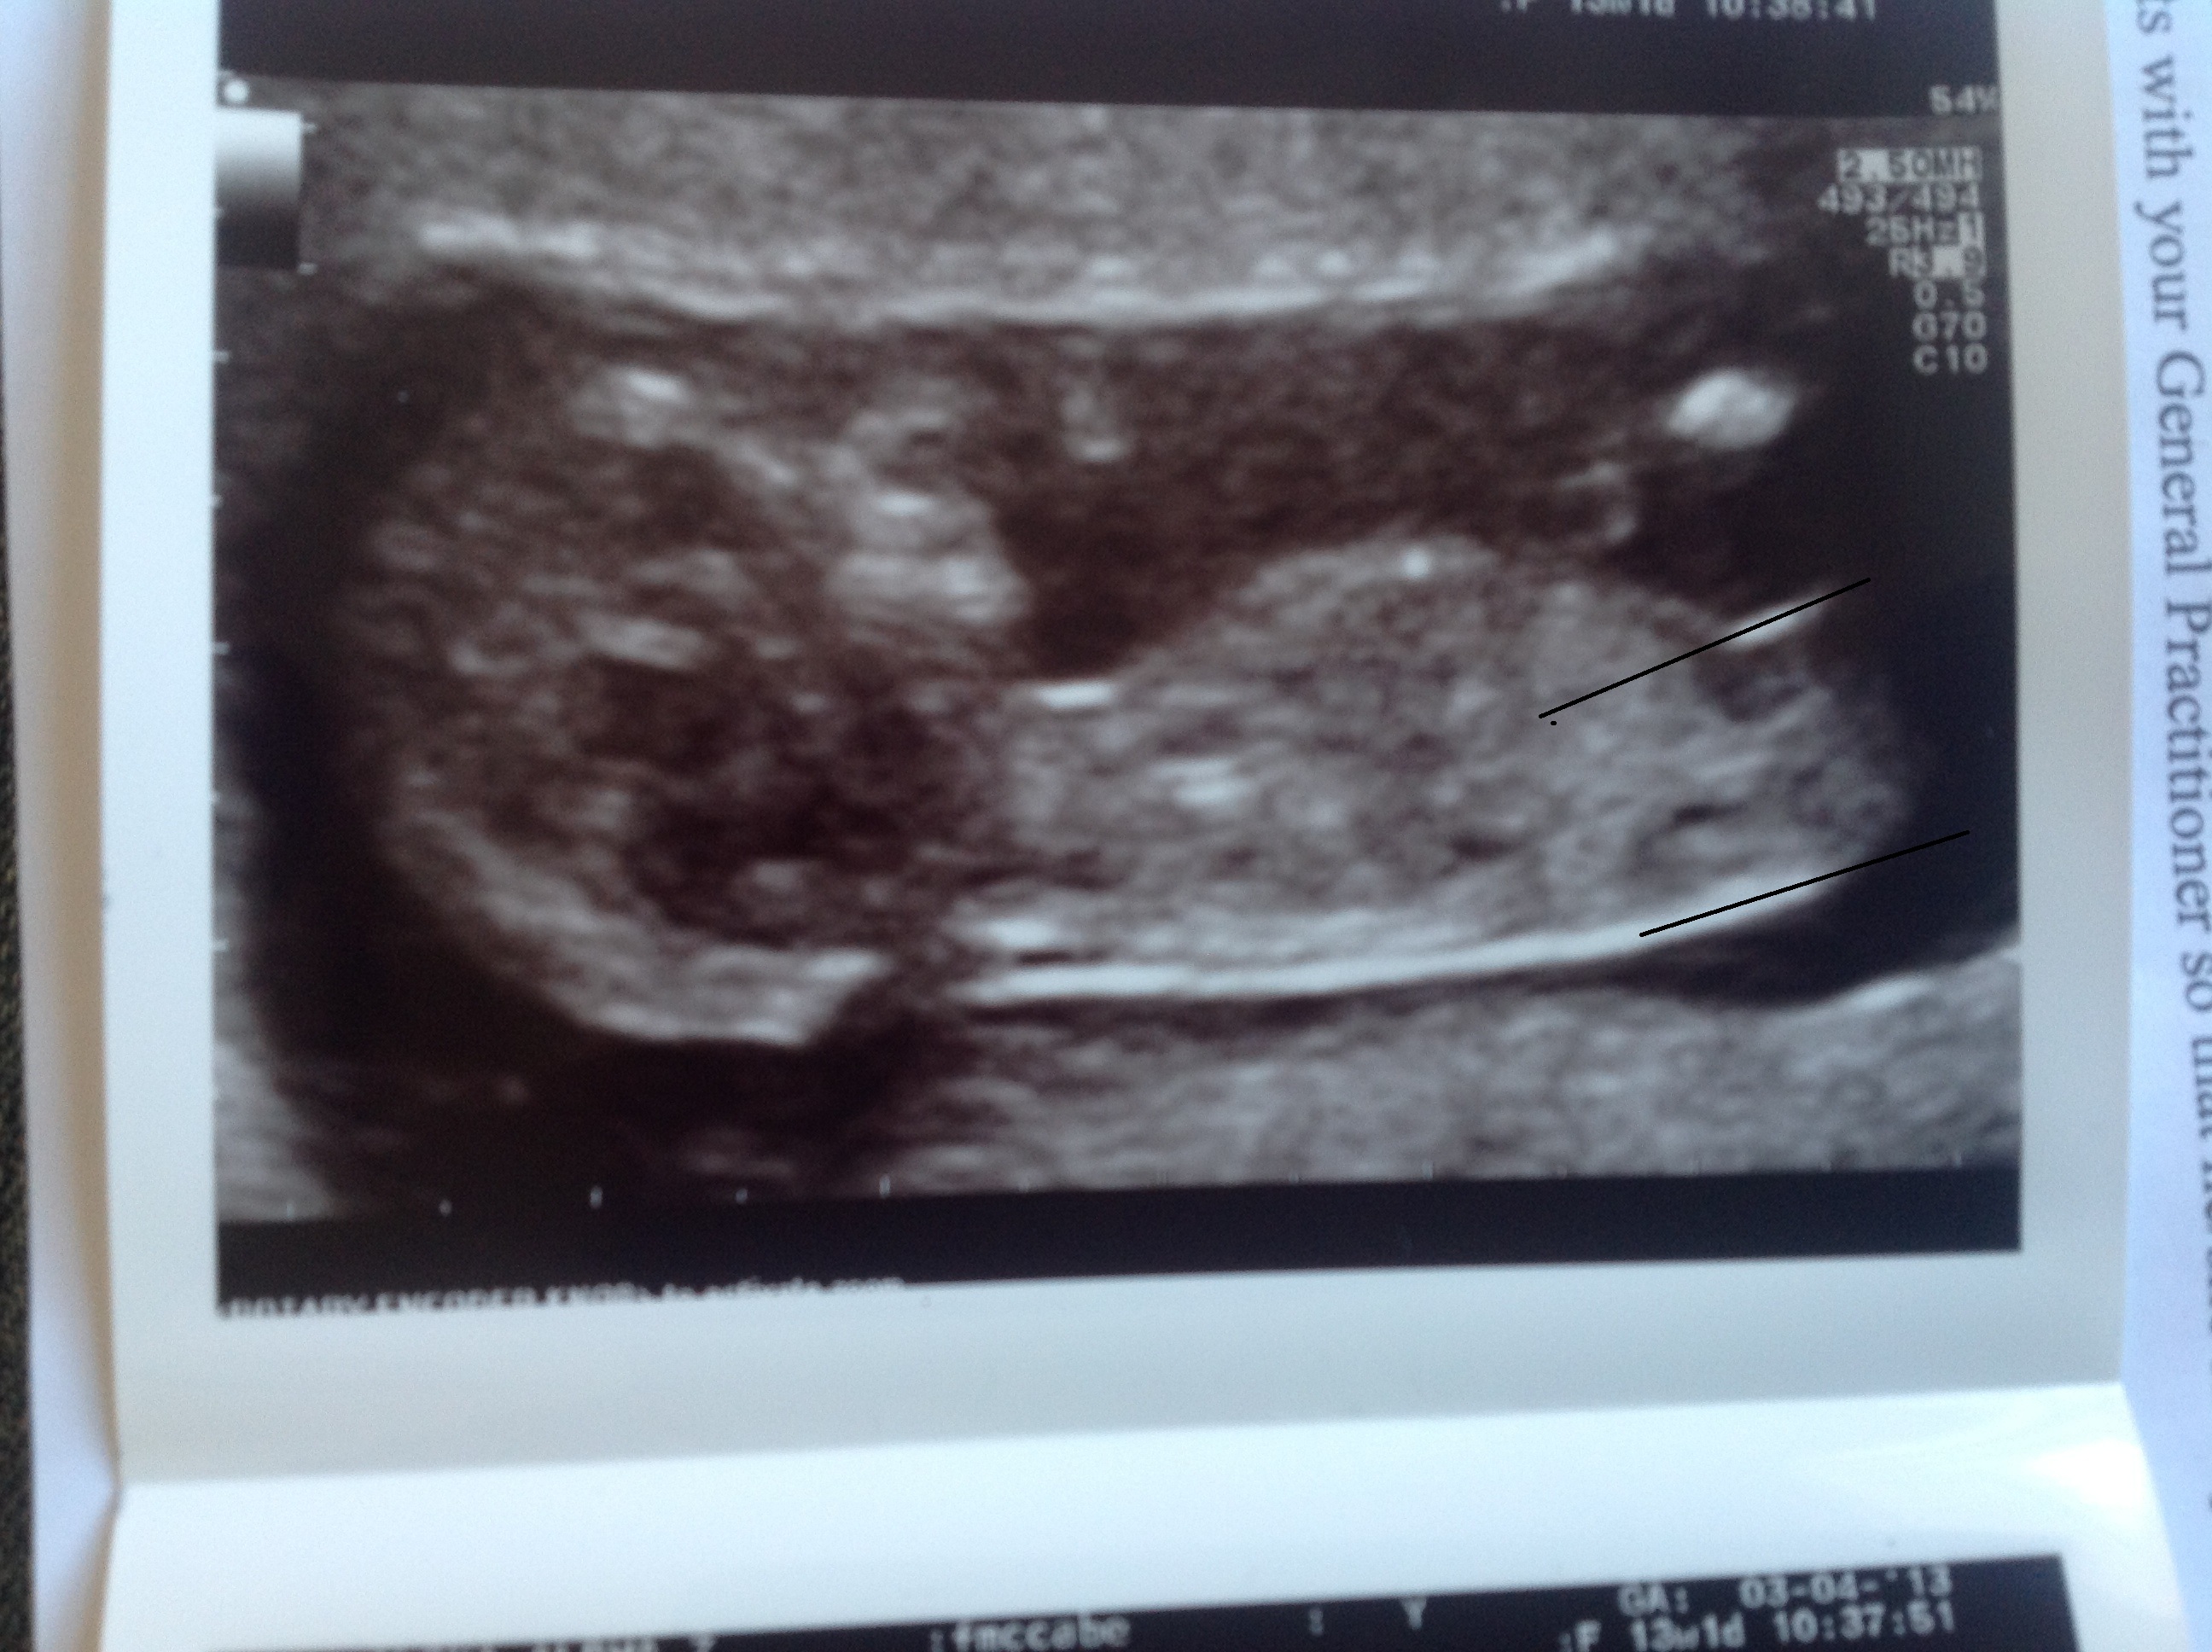

I have lines drew on, but am I right where I have them!!! I am starting to obsess now!!!

Attachment 10306

i think boy, but it'd be easier to guess without the lines in the way. i could see it going either way but i'm leaning boy right now, maybe the lines are throwing me off.

I would also like to see a pic without lines on it. I need to see if there's a bump on the nub or not. And.....do you have more pics?